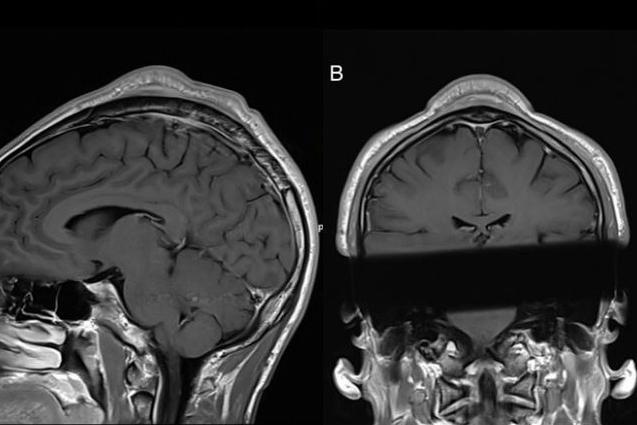

Tạp chí y khoa BMJ Case Reports tiết lộ khả năng chấn thương khi thực hiện quá nhiều động tác "headspin". Một vũ công ở độ tuổi 30 đã phải phẫu thuật cắt bỏ khối u lớn trên đầu.